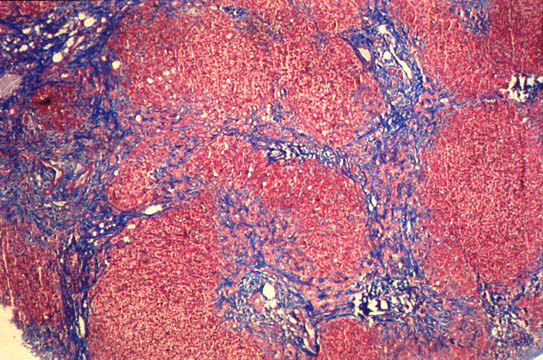

Biliary fibrosis

Fig.72 - BILIARY FIBROSIS: Severe nodular transformation of the liver by porto-portal fibrosis septa without inflammatory cells in clean obstructive jaundice.